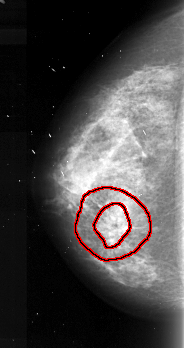

FILE: A_1104_1.LEFT_MLO.OVERLAY

TOTAL_ABNORMALITIES 1

ABNORMALITY 1

LESION_TYPE MASS SHAPE IRREGULAR MARGINS SPICULATED

ASSESSMENT 5

SUBTLETY 5

PATHOLOGY MALIGNANT

TOTAL_OUTLINES 2

BOUNDARY

CORE